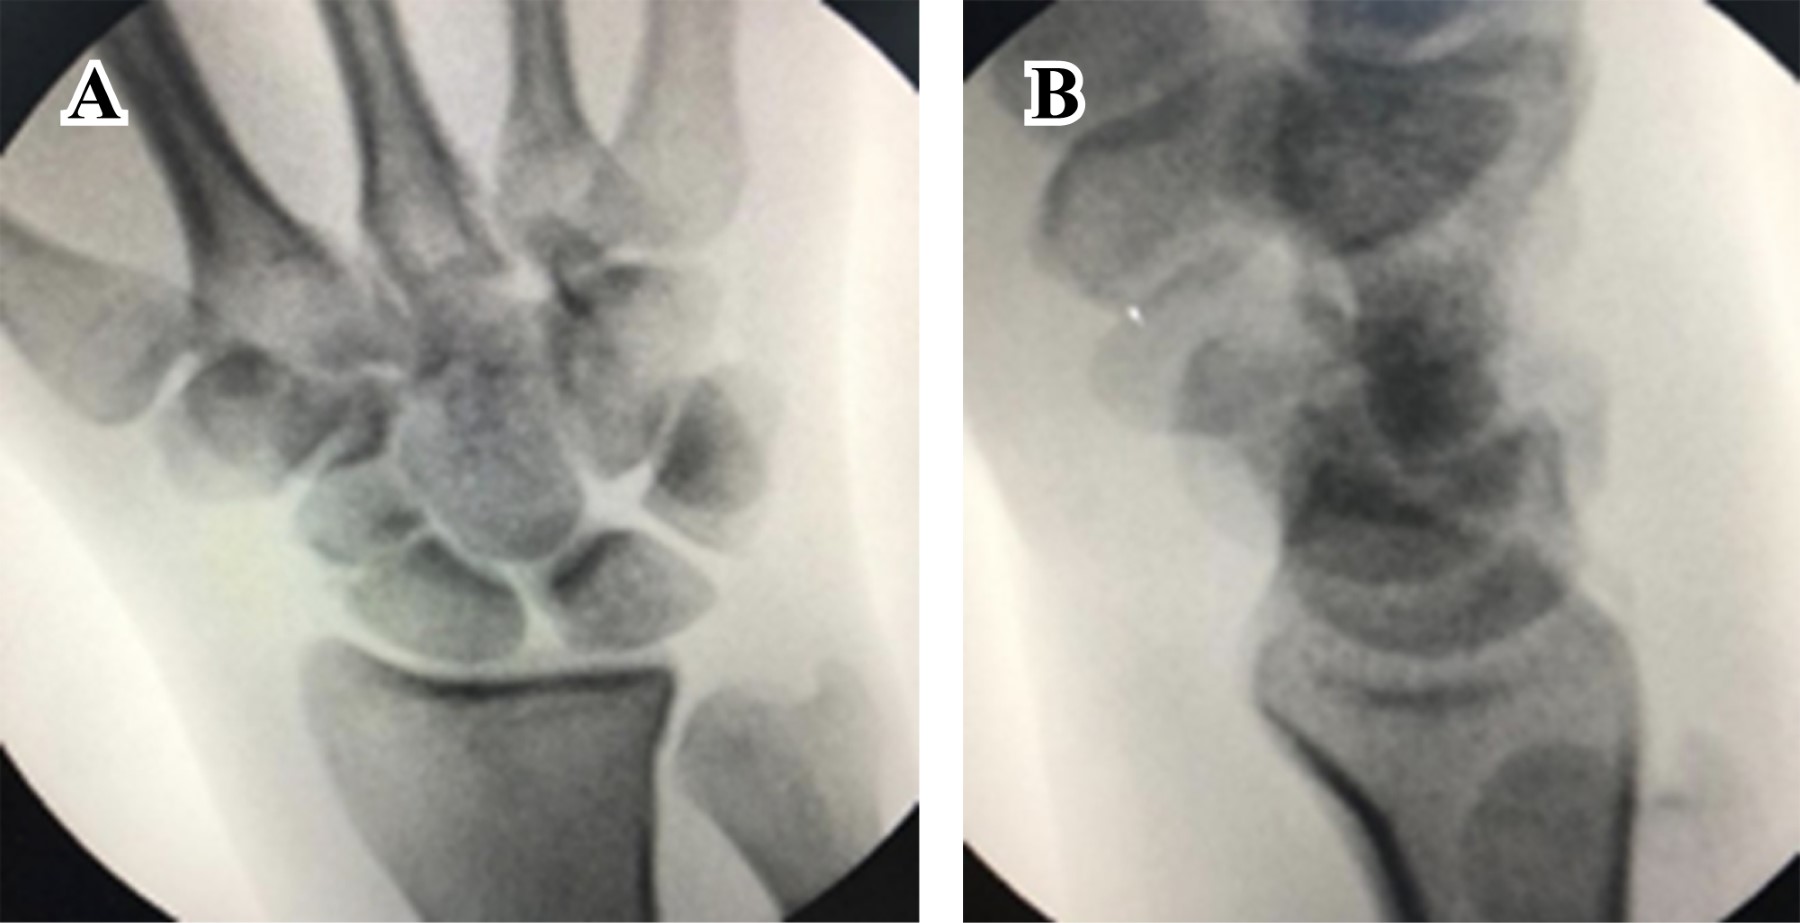

Masculino de 23 años de edad, sano, quien sufre caída del propio plano de sustentación contundiendo mano derecha con mecanismo de hiperflexión. Inicia con dolor, limitación funcional y edema importante en muñeca, motivo por el cual acude al servicio de urgencias. A la exploración física, llama la atención edema y deformidad en dorso de muñeca derecha con limitación funcional a expensas del dolor, sin alteraciones neurovasculares distales. Se realizan radiografías en proyecciones anteroposterior y oblicua de mano (Figura 1); se observa incongruencia entre líneas carpales con sospecha de fractura de escafoides. Se realiza tomografía computarizada (Figura 2), con la cual se completa diagnóstico de fractura luxación transescafo-perilunar.

Figura 1